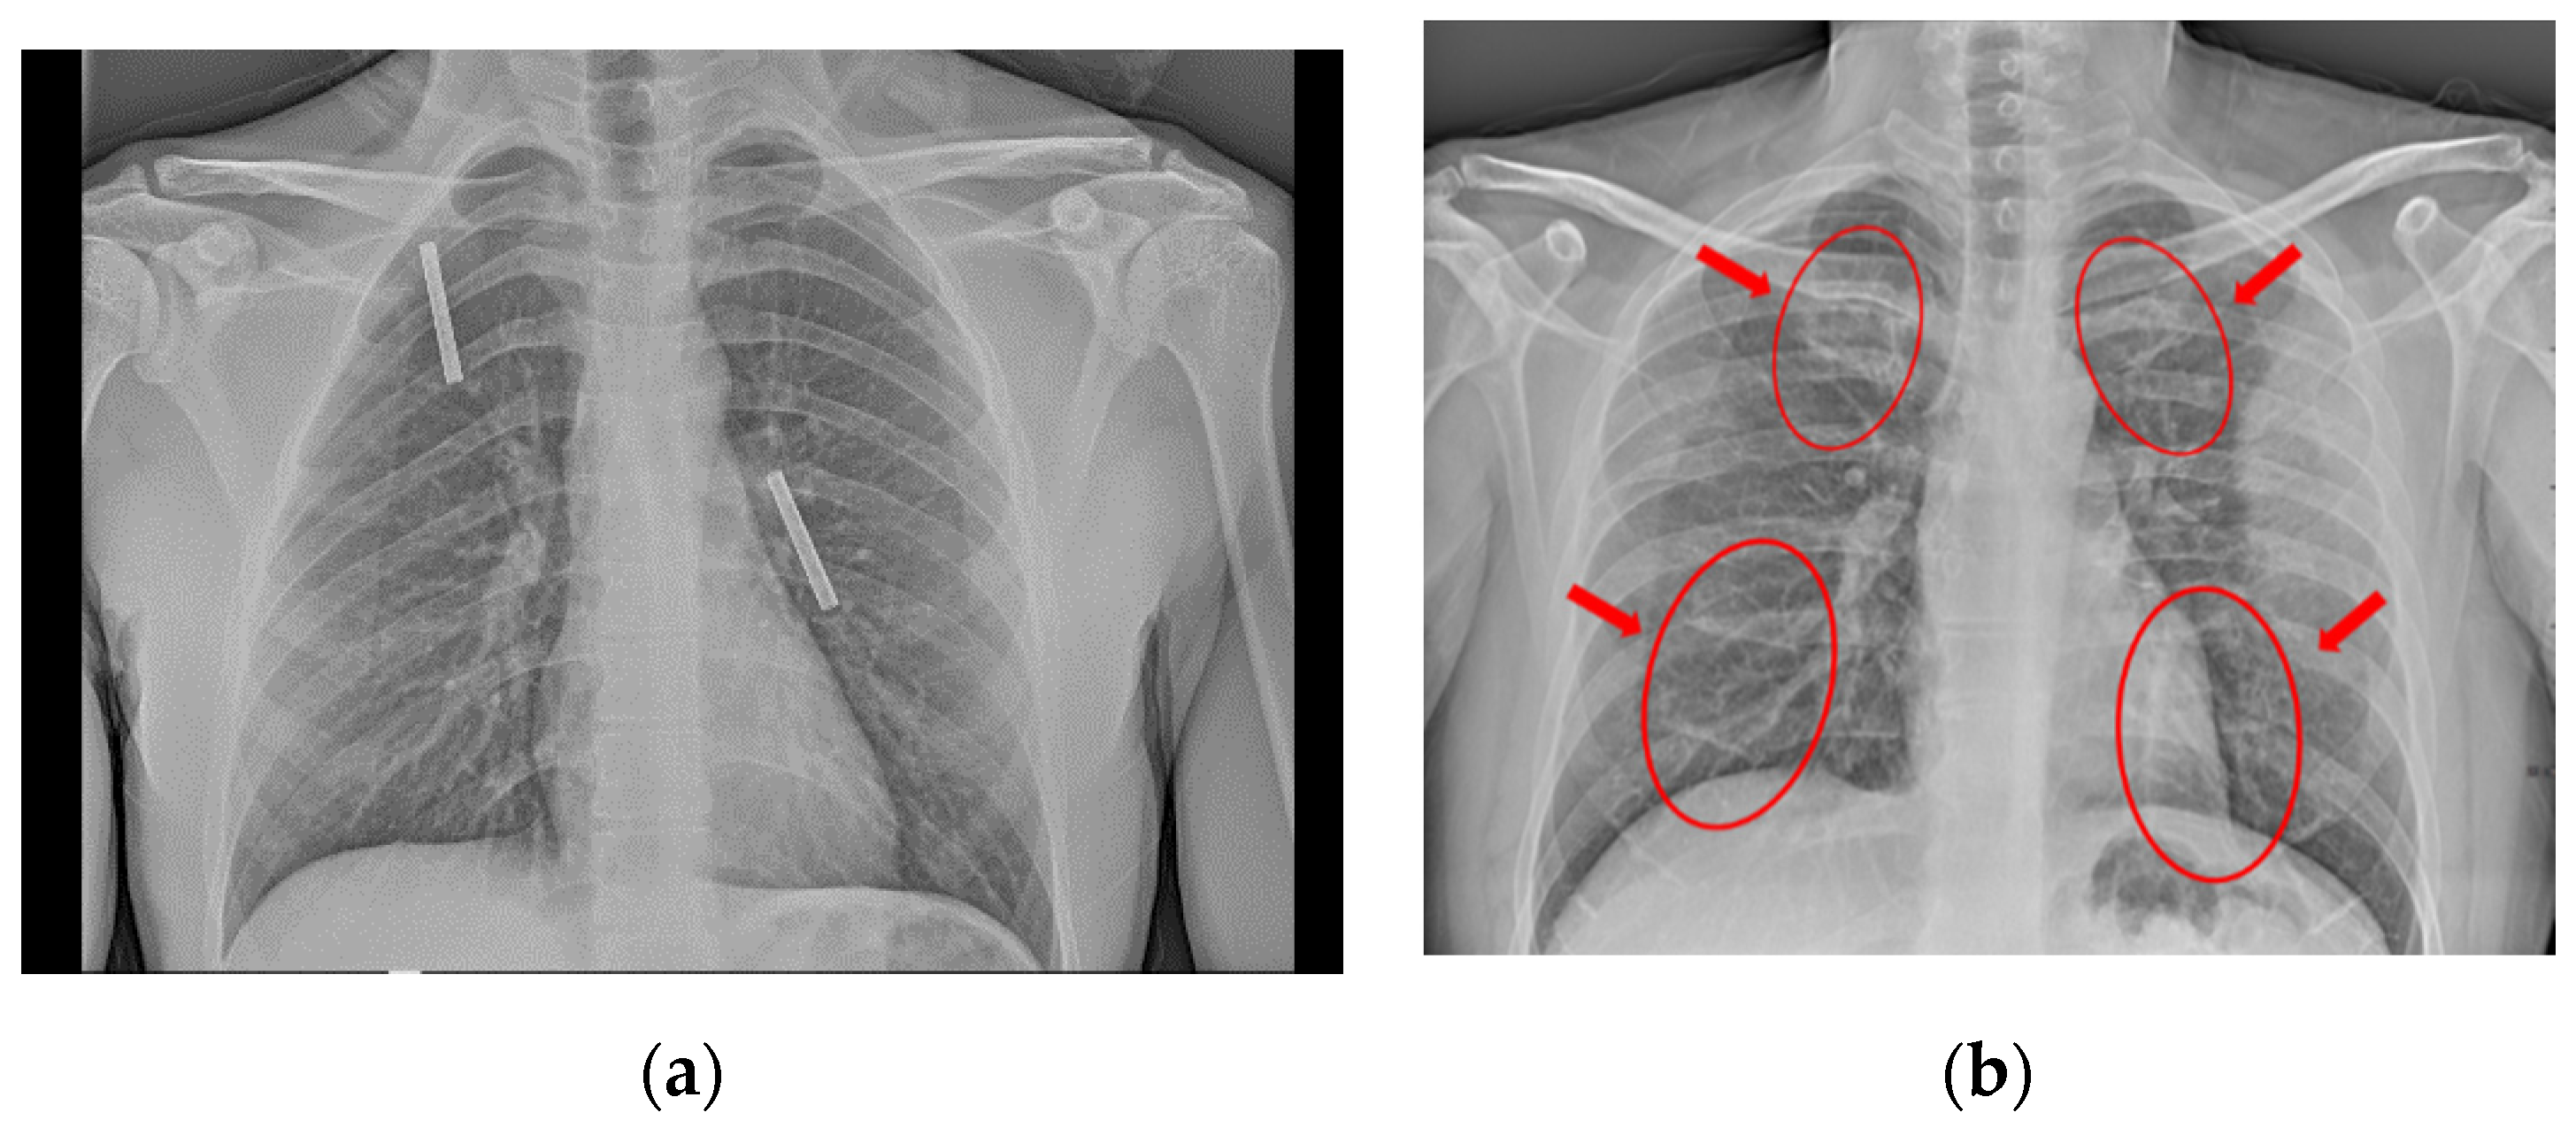

For this type of pneumonia performing a chest x-ray on the. Chest x-rays can reveal areas of opacity seen as white which represent consolidation. In complicated cases of pneumonia perform chest radiography 6 weeks after treatment to verify resolution of the pneumonia and to screen for any underlying predisposing.

Doctors typically rely on a physical exam and tests. Pulmonary consolidation is a non-specific term for pulmonary opacities seen on radiography that are the result from a process that fills the alveolar spaces further discussion here. Baby chest x ray pneumonia.

This chest X-ray shows an area of lung inflammation indicating the presence of pneumonia. However chest X-ray examinations for pneumonia detection are prone to subjective variability 2 3. Please see disclaimer on my website.

It determines the pathogen that could have caused pneumonia. The differential for the radiologic finding of pulmonary consolidation includes blood pulmonary hemorrhage pus infection ie. We investigate whether chest radiographic findings could be used as predictors of severity of childhood pneumonia.

The Radiological Diagnosis Of Pneumonia In Children Pneumonia Full Text

The Radiological Diagnosis Of Pneumonia In Children Pneumonia Full Text